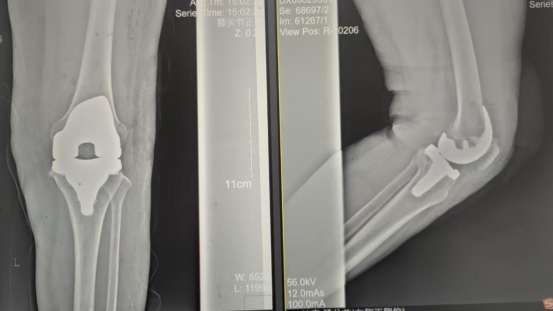

术后影像资料

因张女士患有高血压病2级(高危)、心律失常(窦缓)且伴有肺部熏染等并发症。。。。。。穆志亮主任和叶龙安主治医师凭证张女士的病情制订详细手术方案,,,,,建议在全麻下行“左人工全膝枢纽置换术”。。。。。。

手术当天张女士怀着忐忑的心情进入手术室,,,,,然而陪同着麻醉医师的平和攀谈和手术护士的温馨付托,,,,,在不知不觉中逐步睡着,,,,,手术很是顺遂。。。。。。术后经医护职员的全心治疗与护理,,,,,张女士康复出院,,,,,最终解决了10余年的病痛。。。。。。